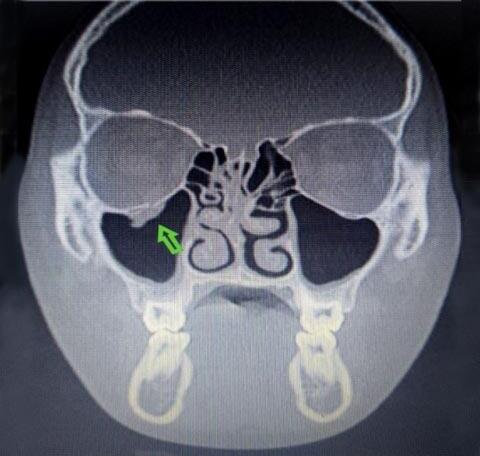

Las fracturas de órbita son lesiones frecuentes en la población pediátrica. Existen distintos mecanismos fisiopatológicos que llevan a presentar este tipo de fracturas. En los niños pequeños, a diferencia de los adultos, la fractura del techo orbitario es más frecuente debido a las dimensiones craneofaciales, la ausencia de neumatización de los senos paranasales y la falta de dentición. Las piezas dentarias permanecen dentro del maxilar superior y de esta forma actúan como un factor protector del piso orbitario. Luego de los siete años, la incidencia de fractura de piso aumenta y comienzan a producirse las llamadas “blowout”, superando a la del techo de órbita. A esta edad el cráneo se asemeja al del adulto, al igual que los puntos de debilidad de las paredes orbitarias, siendo las más delgadas y pasibles de lesionarse la pared medial y el piso de la órbita. (Figura 1) Durante la infancia, los huesos presentan mayor elasticidad, motivo por el cual al ocurrir una fractura, el trazo fracturario tiende a volver a su posición original, las conocidas fracturas de tallo verde. Al producirse el trauma aumenta la presión dentro de la órbita la cual se transmite hacia los

puntos más débiles rompiendo los mismos, teniendo en cuenta que la misma es una cavidad no expansible, lo que permite el paso de las estruc turas blandas or bitarias hacia espacios de menor presión (desde la órbita hacia los senos paranasales adyacentes) (1-2-3). Al finalizar el trauma la presión disminuye y el trazo fracturado vuelve a su posición normal lo que genera en algunos casos un atrapamiento del contenido herniado hacia el seno ya sea músculo o tejido orbitario (fractura tipo trapdoor ). Esto contrasta con el adulto, donde los huesos son más maduros, quebradizos y menos flexibles. Al recibir un golpe de iguales características, el piso sufre múltiples fracturas que se desplazan hacia el antro en lugar de permanecer articuladas, fracturas que llamamos “opendoor” (4).

Las fracturas de piso de ór bita pueden provocar diplopía, enoftalmos, hipoglobo, parestesia del nervio infraorbitario, oftalmoplejía, incluso desencadenar el reflejo oculocardíaco en caso de atrapamiento muscular (también conocido como fenómeno de Aschner o reflejo trigéminocardíaco) sumando al cuadro síntomas vagales tales como vómitos, náuseas, hipotensión, síncope, bradicardia (5). El diagnóstico es clínico acompañado de imágenes de tomografía (TC), estudio de elección para este tipo de pa -

Se describe a la WEBOF con tres pilares característicos: 1) evidencia discreta de fractura en los estudios de imagen; 2) restricción en motilidad ocular; y 3) traumatismo mínimo o nulo de los tejidos blandos (de ahí el término "ojos blancos") (5). Y a ellos se suma la presencia o no de síntomas vagales ya previamente descritos.

PRESENTACIÓN DE UN CASO

Un paciente masculino de 13 años, sin antecedentes médicos significativos, fue derivado a nuestra consulta oftalmológica debido a una fractura en el piso de la órbita derecha, resultado de un traumatismo contuso durante un partido de rugby. Antes de la consulta, experimentó varios episodios de vómitos durante aproximadamente 5 horas después del incidente. Al ex aminarlo, se encontró que su agudeza visual era de 20/20 en ambos ojos, con reflejos pupilares normales, presión intraocular y fondo de ojos dentro de los límites normales. En el ojo derecho, se observó una conjuntiva blanca con equimosis y leve edema en el párpado inferior (Figura 2) La motilidad ocular reveló una limitación en la supra e in fraducción del ojo derecho, con diplopía en dichas posiciones pero ausente en posición primaria (Figura 3) . Por otro lado, los episodios repetidos de vómitos antes de la consulta sugirieron la posible presencia de un reflejo oculocardíaco. La tomografía computarizada previamen te realizada en otro centro mostró la fractura en el piso de la órbita y el signo de la gota (Figura 4) , sin compromiso de los músculos extraoculares. Ante estos hallazgos, se solicitó una resonancia magnética de órbita, que reveló herniación del tejido adiposo orbitario hacia el seno maxilar, causando atrapamiento del músculo recto inferior (Figura 5)

Figura 4. Tomografía de órbita y senos paranasales. Corte coronal, ventana ósea. Se observa trazo fracturario en piso de la órbita derecha con el signo de la gota.